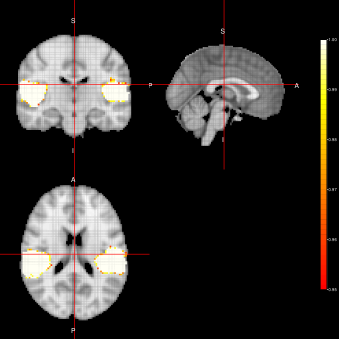

Figure 3: Activation Maps for the ”voice localizer” example obtained when using the FFBS algorithm under three different distributions (Marginal, Joint and LTT) related to the state parameter.

From figures 2, 3 and 4, we can see the activation maps obtained for the ”voice localizer” experiment using the method proposed in this work. From those images, we can say that the three algorithms (FEST, FFBS and FSTS) under the three different distributions (Marginal, joint and LTT or average distribution) successfully identify the temporal activation due to voice and non-voice sounds stimulation, nevertheless there are some slight differences among those maps worth mentioning. For instance, the maps obtained when using the FFBS algortihm allows for the identification of a broader activated region from the temporal cortex, however, on the other hand, it allows activations to appear (false-positive activations) on brain regions that should not be involved with this ”voice localizer” experiment. On the other hand, more conservative results seem to be obtained when using FEST and FSTS algorithms, but with less false activations.